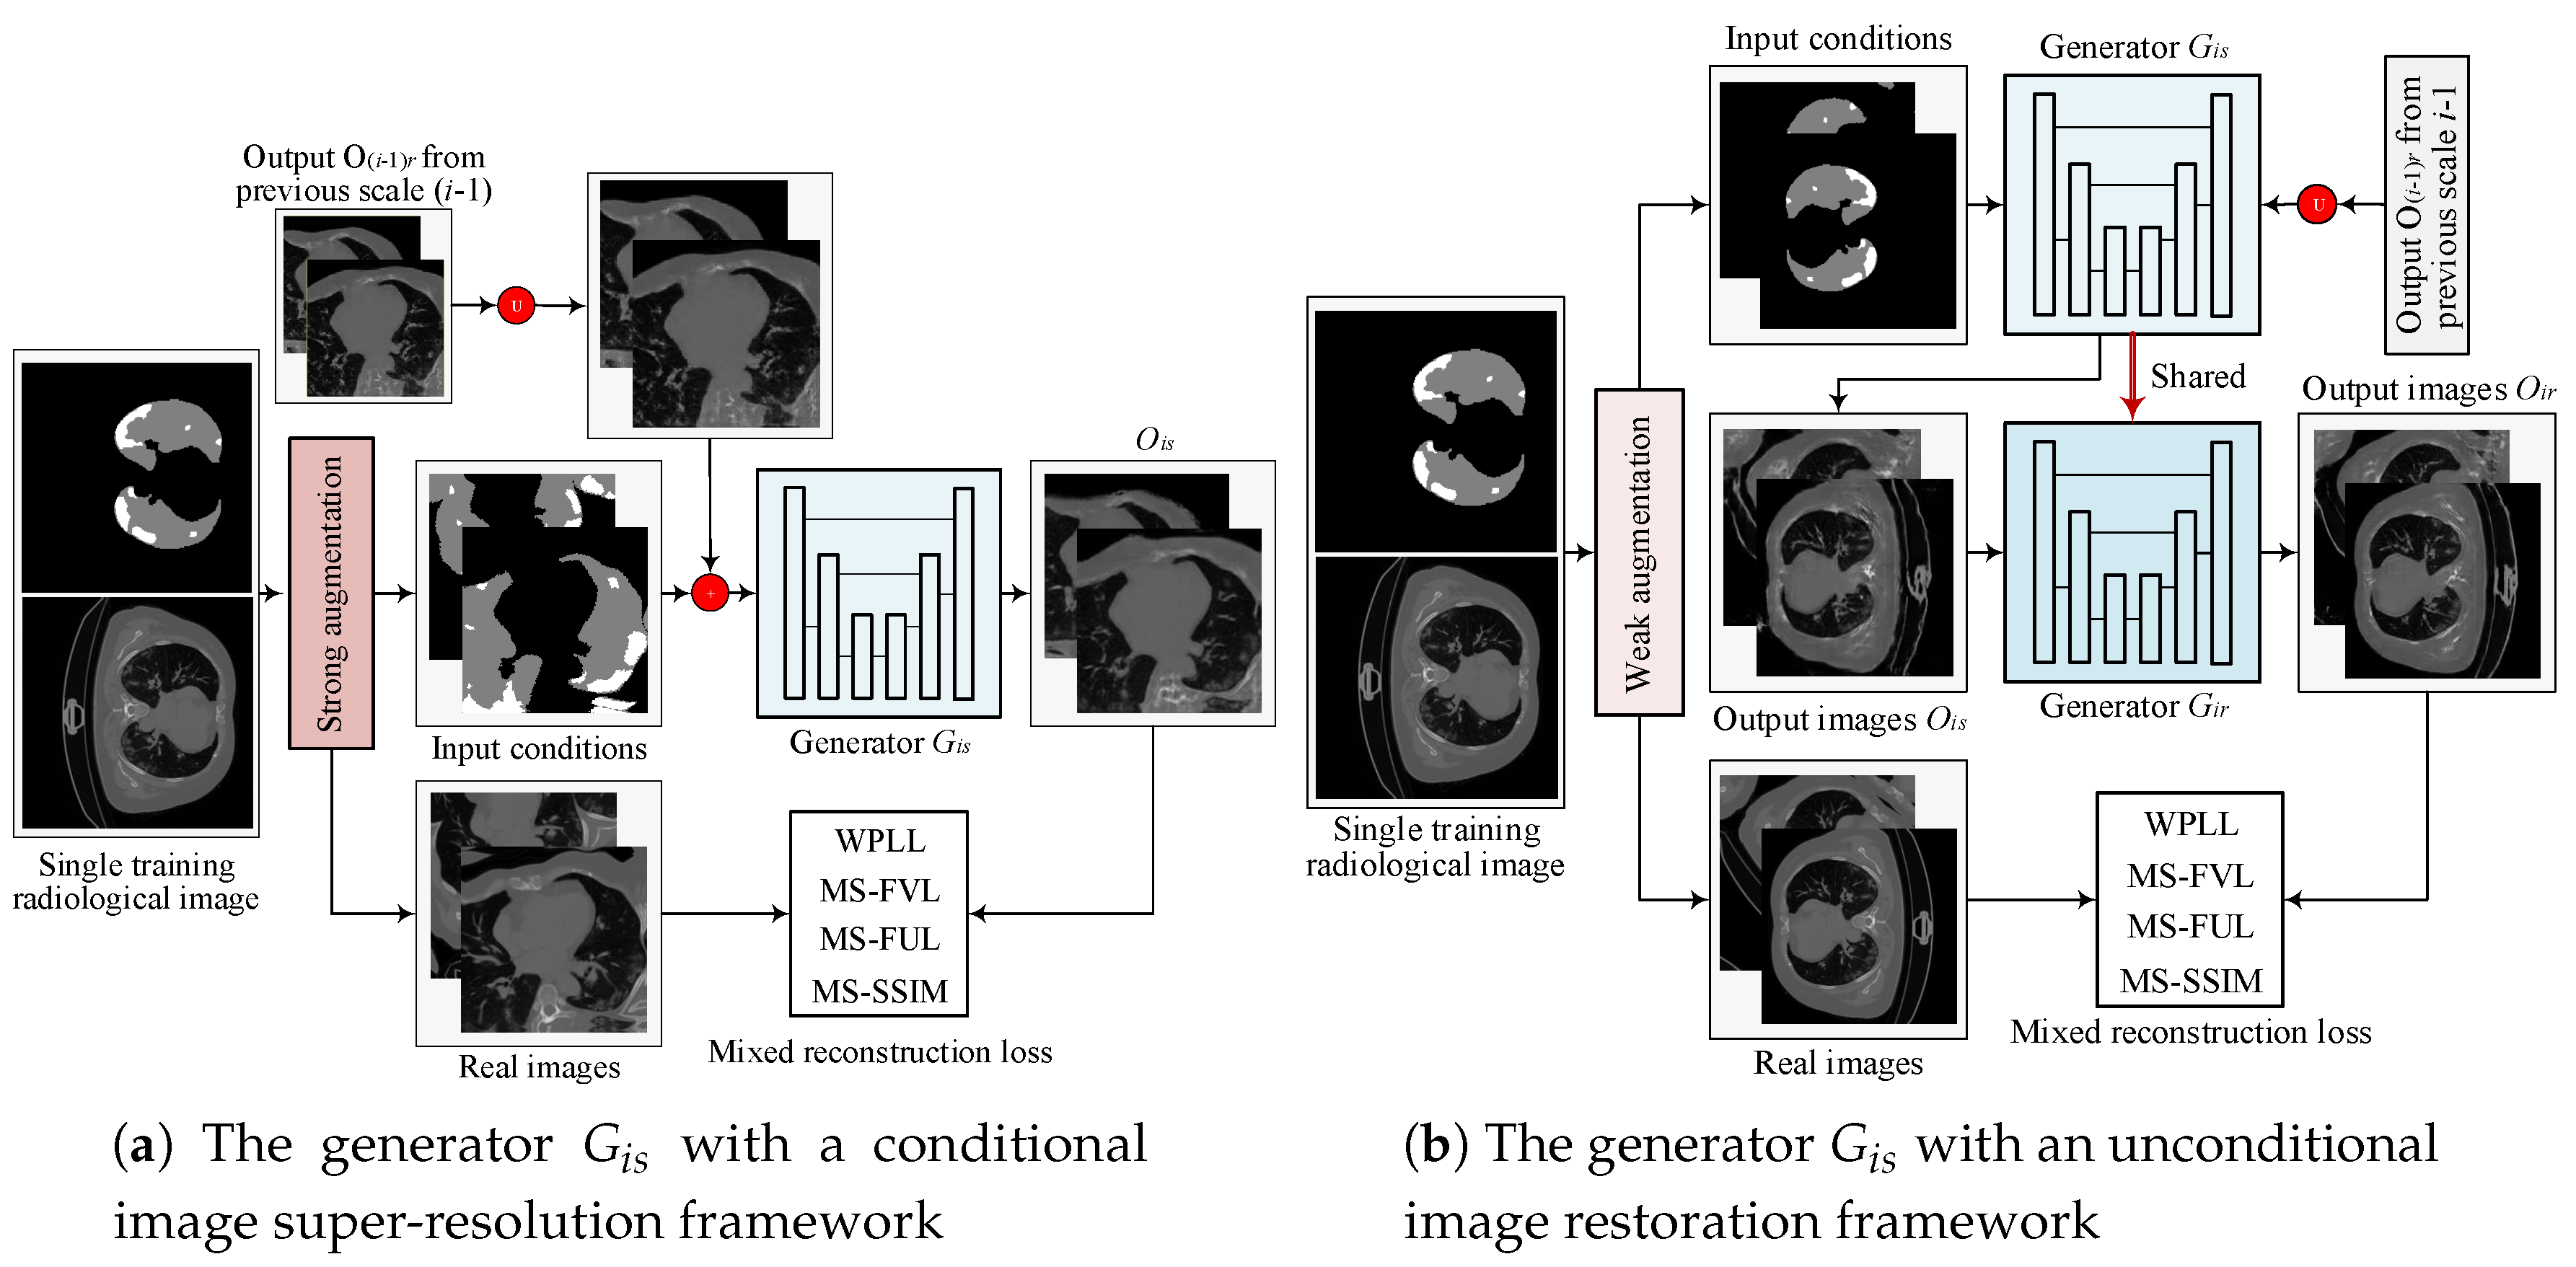

2.1.1. Multi-Scale Architecture with a Pyramid of Two-Stage GANs

2.1.2. Objective

2.1.3. Hierarchical Data Augmentation

- SA is critical for to generalize to different input conditions.

- WA helps to fit the real image distribution without introducing additional learning burden.

- Decreasing the intensity of SA along with the increasing of image scales can handle the balance between fitting conditions and fitting images well.